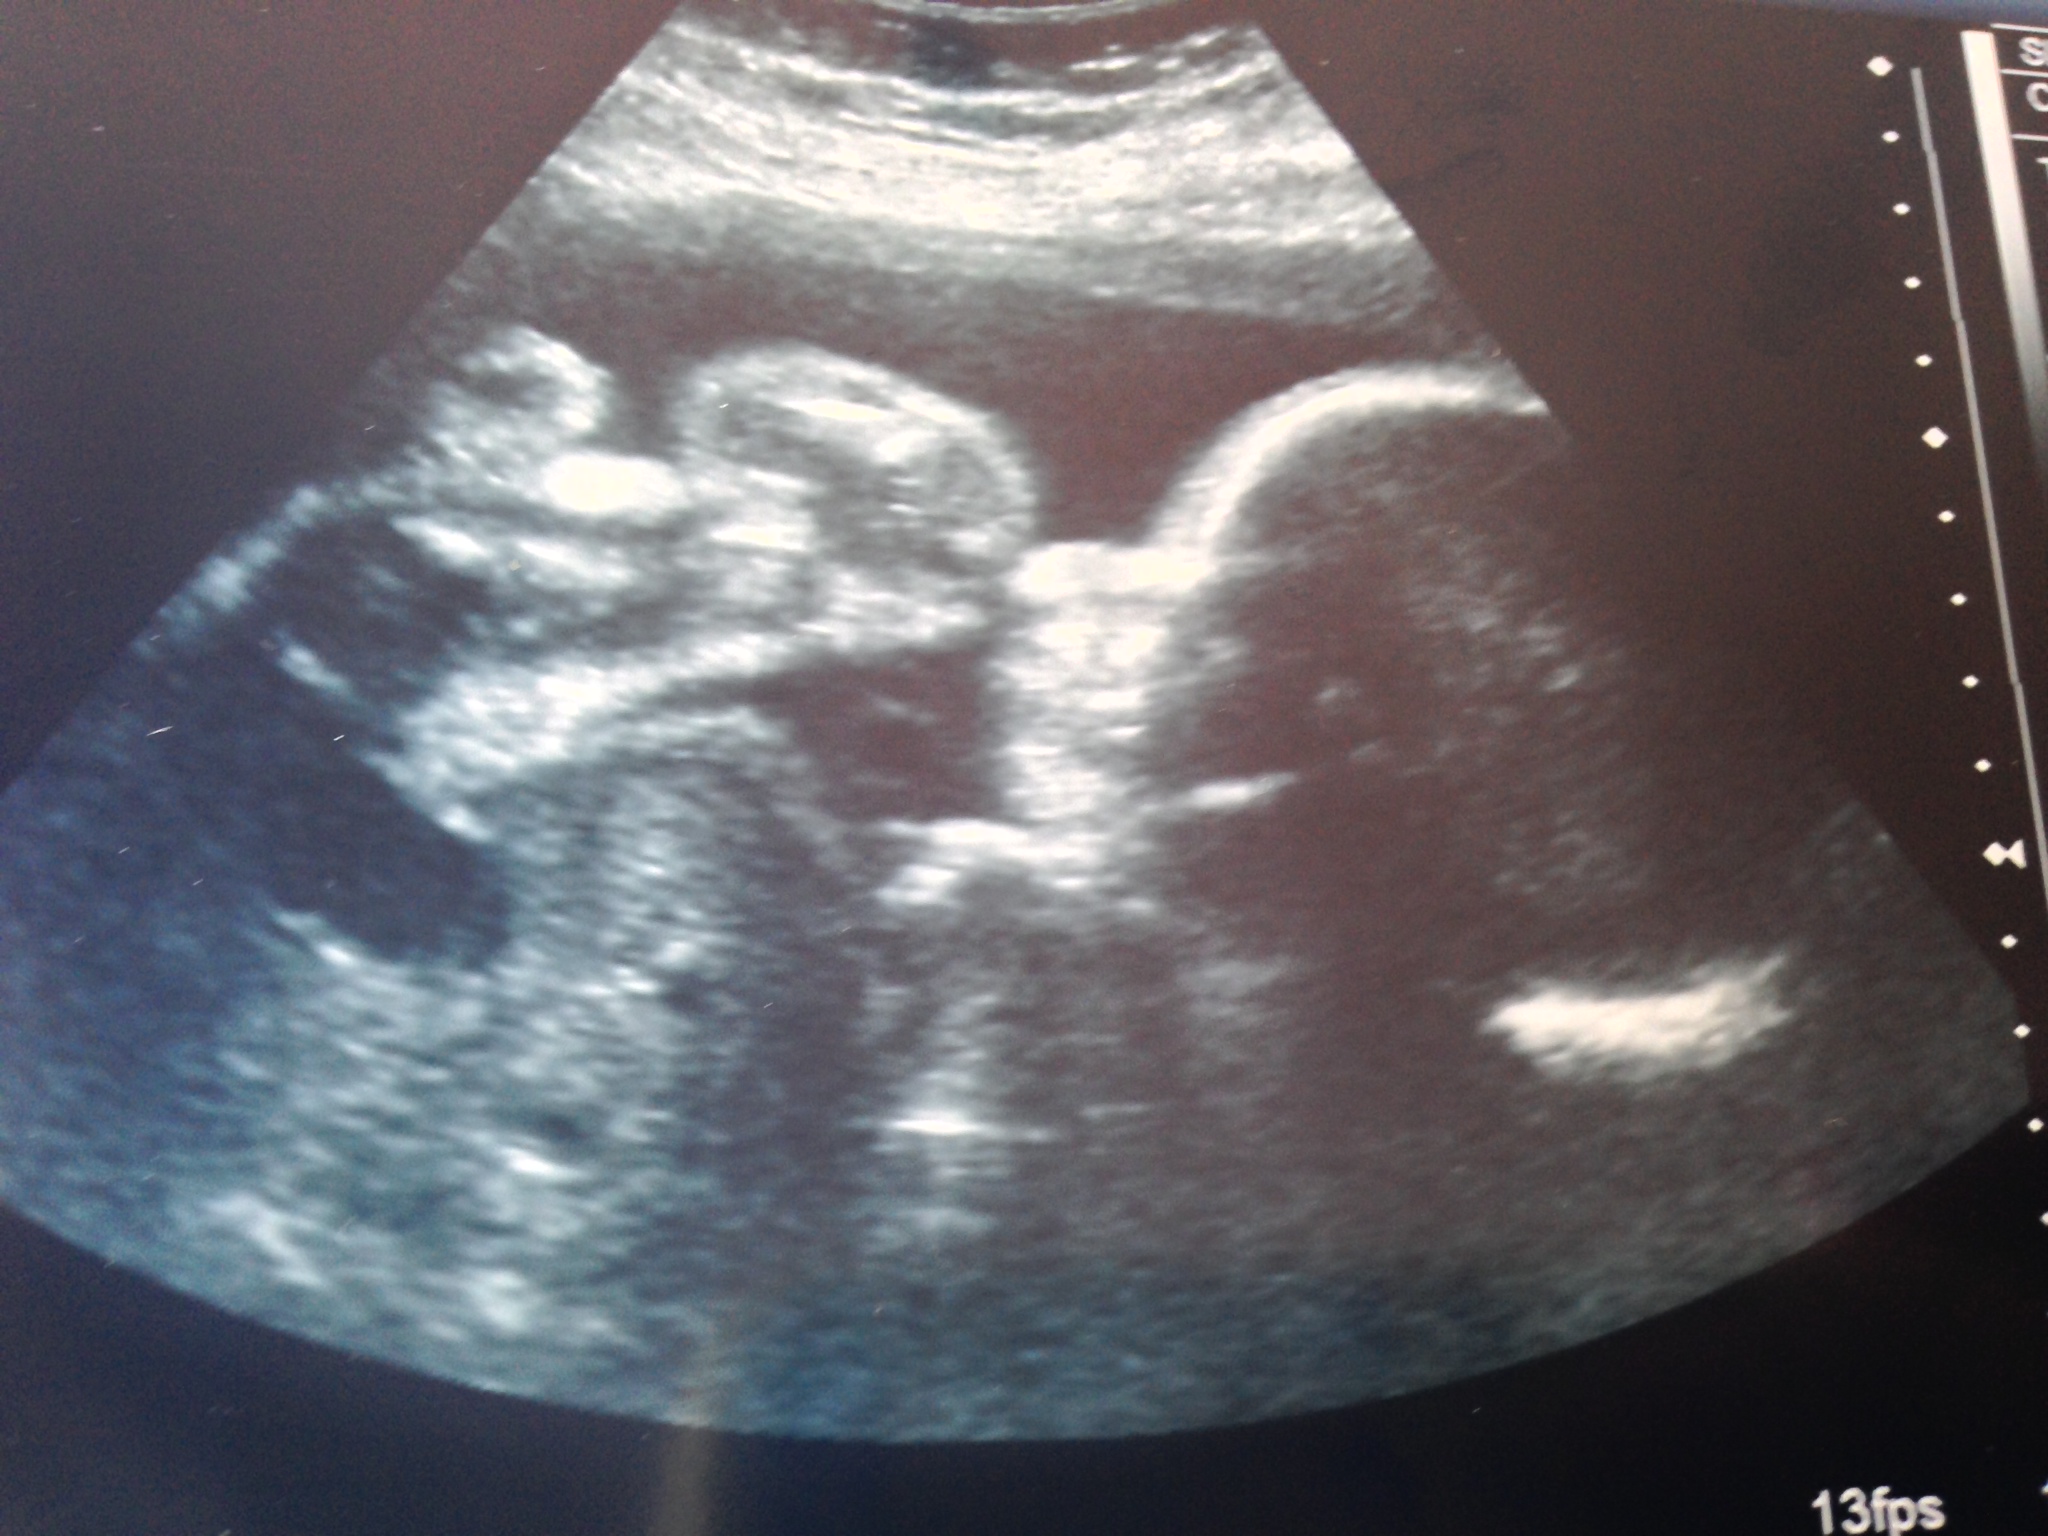

The next day was my Dr. appt. and it was decided that I should have another FFN test done and a cervical length check, “just to be on the safe side”, which I have now heard multiple times. It’s a good thing I guess. You know what else I have heard 100,000,000 times? Okay maybe not that many times but any time someone in the medical field looks at my stomach, I always get asked where the vertical scar came from. Then I tell them the story and the responses range from “Oh ya, I remember hearing about that” to ” Oh wow, that must have been scary.” When the ultrasound is done to check the cervix, I get the pleasant, “Oh, there is your placenta right there, good thing we didn’t do a manual cervical check.” Like they’re surprised to see that I still have the previa. . Oh you know what else the nurse asked me as she was doing the FFN test? “Is this your last baby?” “Hell ya” I said. She said she thought that was probably a good idea. I couldn’t agree more.